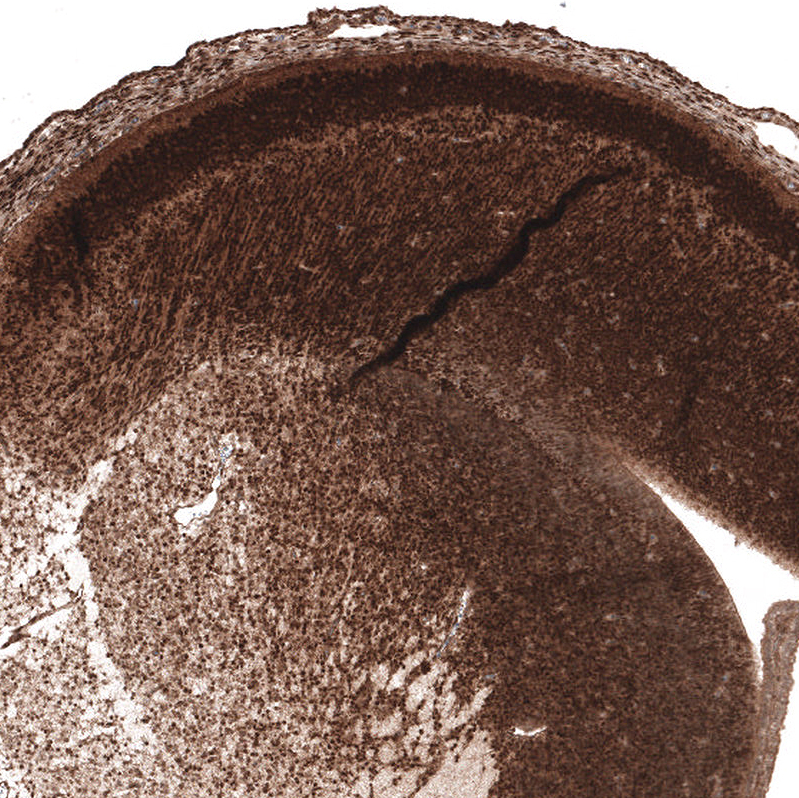

Immunohistochemical staining of human cerebral cortex shows moderate nuclear positivity in neuronal cells.